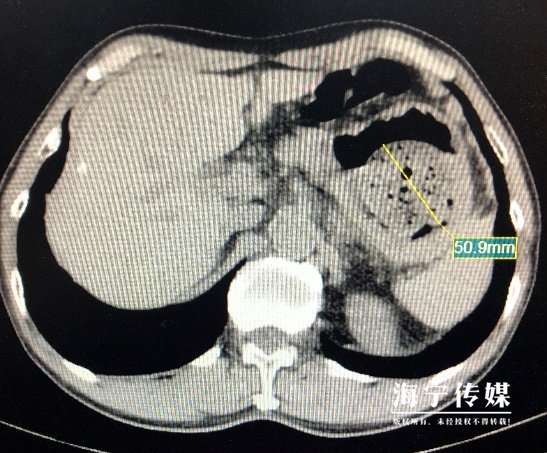

接诊的朱忠杰大夫了解孙大叔的情况后,首先给他做了腹部CT,提示胃内有一个直径约5cm高密度影。

腹部CT提示胃内有一个直径约5cm高密度影